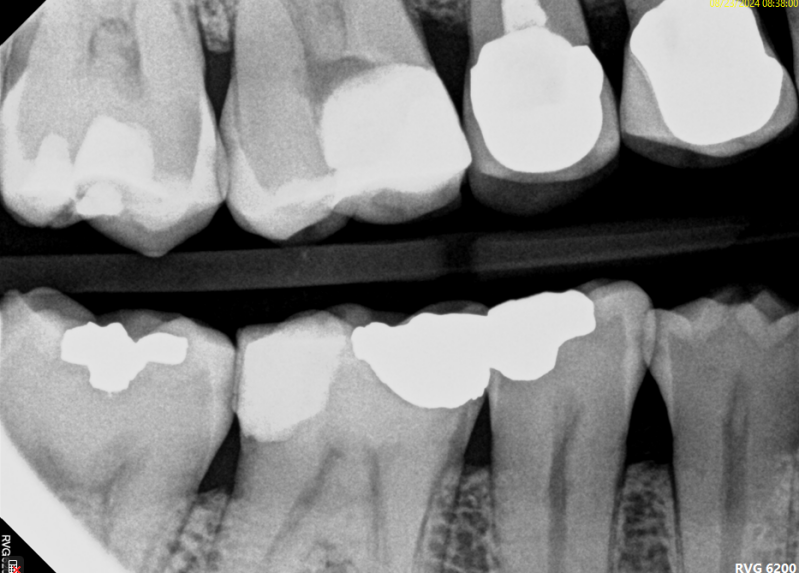

Case: RCT on Tooth #30

54-year-old female, osteoporosis (on oral bisphosphonate therapy), no known allergies.

Dx: Pulp necrosis and asymptomatic apical periodontitis.

Tx: Non-surgical root canal therapy (RCT).

Reflection

Given the patient's long-term bisphosphonate use (>5 years), root canal therapy was selected over extraction to minimize MRONJ risk, despite limited restorability. Treatment was complicated by a highly calcified and merging mesial root system. Patient remained asymptomatic and successfully proceeded with post and core buildup after two months.